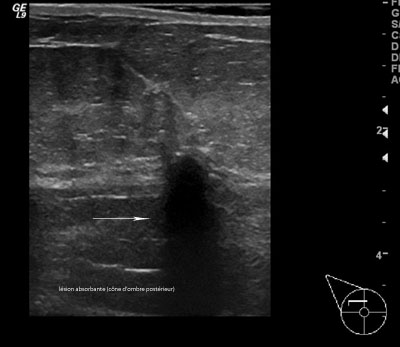

Masse maligne absorbante